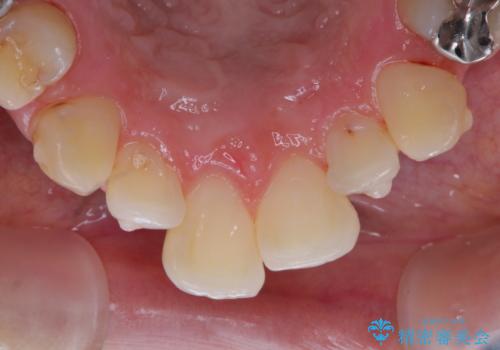

- インビザラインで矯正治療中にクリーニングを希望されました。PMTC60分コースで、クリーニングと歯ブラシ指導を行いました。

磨けているようでも、染出しをして目に見えるプラーク(歯垢)を確認することで、より正しいブラッシング方法を身につけることができます。インビザライン中は、歯にアタッチメントをつけるため、歯の表面がデコボコしてプラークが付きやすい状態になります。毎日のケアでしっかりと汚れを落として虫歯や歯周病・口臭のリスクを減らしていくことが大切です。定期的にメンテナンスを行い、ケアがどれくらい出来ているか確認したり歯科医院で専門的な機械や器具によるPMTCを行うことをおススメします。